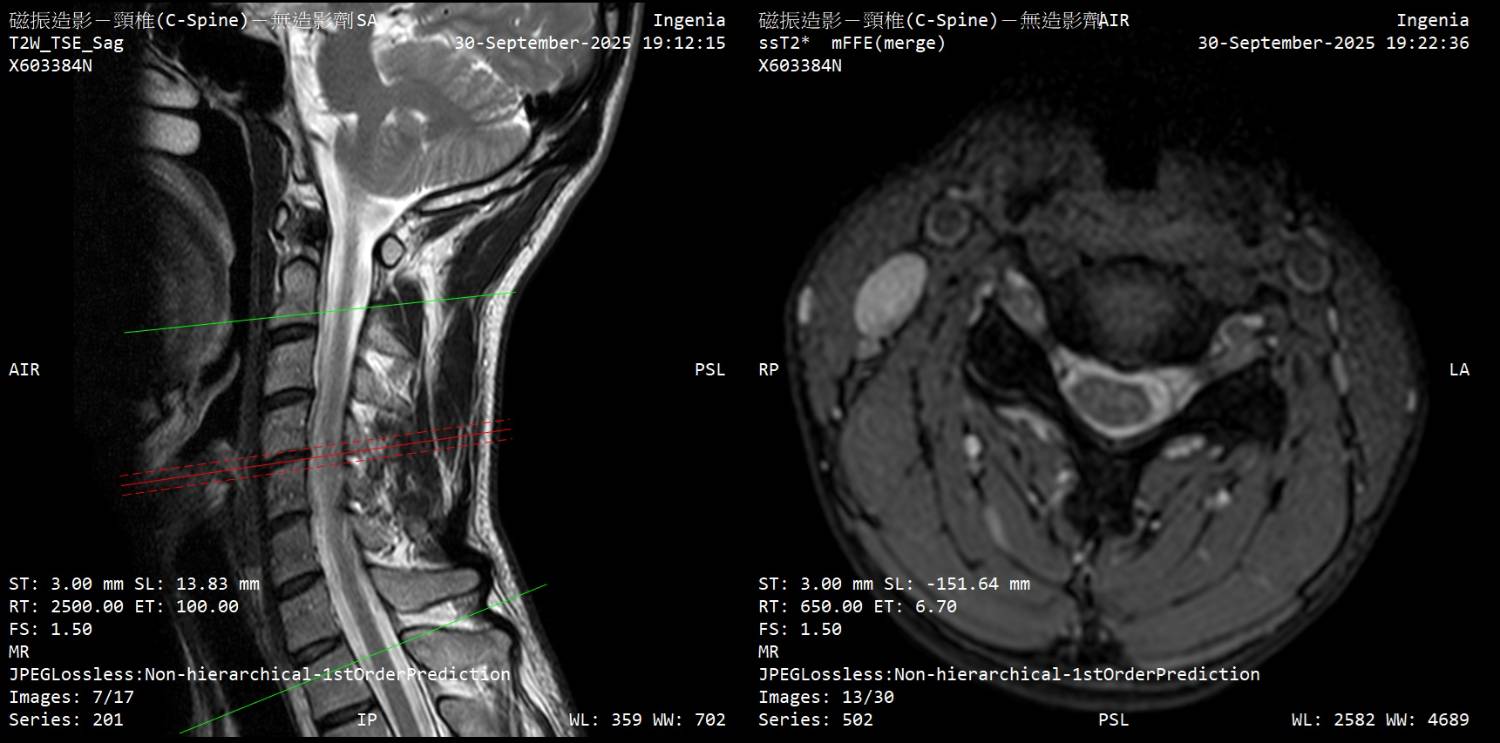

大家好 因为下列症状从2月开始断续发生,8月运动伸展上背後症状加剧 前往神经内科、神经外科就诊,目前不知道下步该往什麽方向? 该矫正姿势(脖前倾)? 复健科拉脖子? 寻求其他意见? 再观察? 症状 - 起床双手握不紧的感觉,白天正常 - 双手指尖感觉迟钝、左手臂外侧微麻感 - 双脚底有微微电流感(静止才感觉得到)、肌肉不定时抽动感、右小腿肚微麻 - 近半年有两次躺着以为有地震,结果没有震 检查 - 霍夫曼测试阳性、双膝反射增强 - 动作诱发电位正常、感觉诱发电位颈到手异常 11.3ms (标准<11ms) - 上肢神经传导正常 (一家正常/一家右正中神经异常) - 下肢神经传导左小腿/脚背异常 (以前受伤後遗症) 诊断 - 神内医师:颈椎有压迫、C5-C6黄韧带增生,建议先复健看看 - 神外医师:没有问题,应该是双手腕隧道症候群 颈椎MRI (全部) https://drive.google.com/drive/folders/1AmMB51gjrYYUIF8by9BEnTz1ahY3hbVp 文字报告 Unremarkable curvature of cervical spine No obvious herniated disc No obvious neuroforaman stenosis Suggest correlate clinical data. IMP: Unremarkable finding 神内医师判断可能压迫的部份 https://i.meee.com.tw/0E4JmY7.jpg

https://i.meee.com.tw/t3QgaWs.jpg

https://i.meee.com.tw/CsUmHf3.jpg

https://i.meee.com.tw/0C6bI5t.jpg